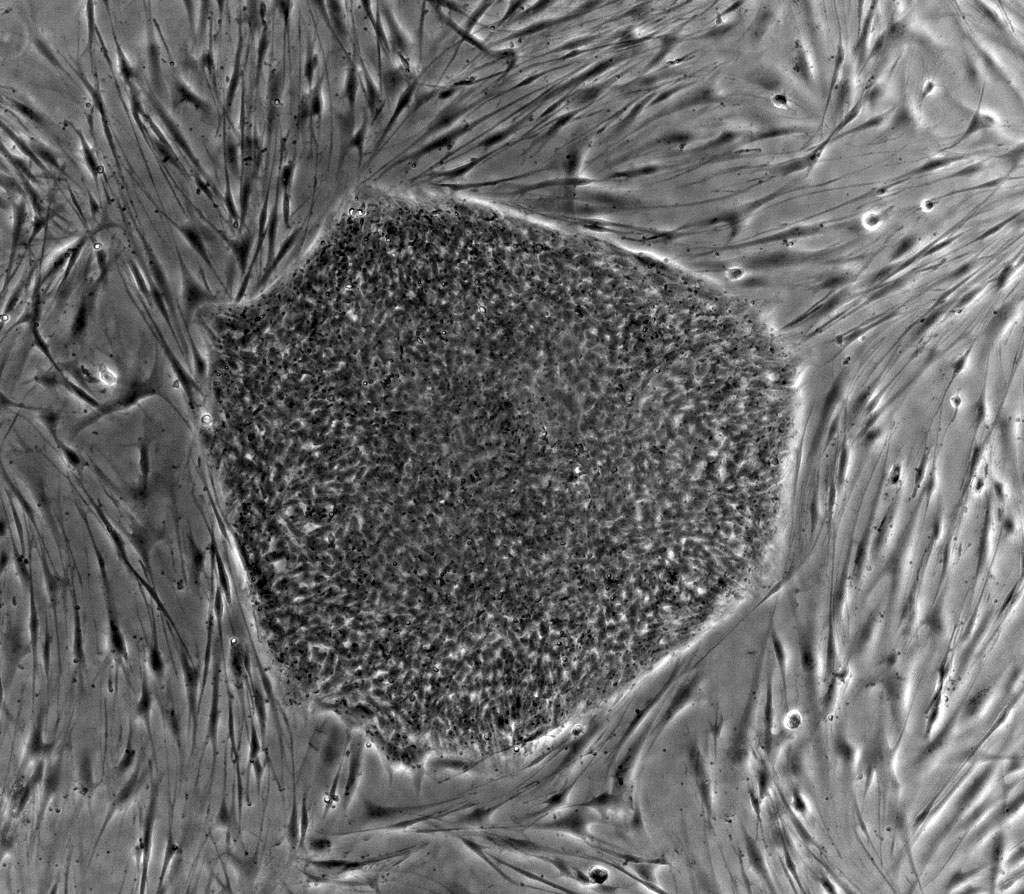

El investigador Joan Massagué ha anunciado este lunes que han descubierto que la metástasis del cáncer de mama podría evitarse atacando la proteína SRC, una pieza vital en la alimentación de las células cancerosas letales que durante años se alojan en estado latente en órganos vitales, antes de manifestarse.

El científico ha explicado, además, que hay un medicamento en el mercado, que se utiliza para tratar la leucemia mieloide crónica cuando fracasa el primer tratamiento, que actúa contra la proteína SRC, lo que significa que "si se elimina esta pieza se corta el suministro a estas células latentes malignas para que vivan".

El científico ha recordado que la metástasis es lo que dificulta a los médicos el tratamiento del cáncer y que el 90% de los fracasos se debe precisamente a que a partir del tumor primario hay una invasión de células distantes que no se logran eliminar con los tratamientos actuales, y que al cabo de años, incluso décadas, consiguen hacer colonizaciones metastásicas en órganos vitales.

En su discurso ha insistido en que cuando se inicia un tumor cancerígeno, y antes de que se diagnostique, ya hay células tumorales que viajan a través de la circulación sanguínea a otros órganos, y que aunque el 99,99% de ellas mueren por condiciones extremas, unas pocas vivirán y lograrán infiltrarse en los pulmones, el hígado, el cerebro o en el riñón para reaparecer más tarde.